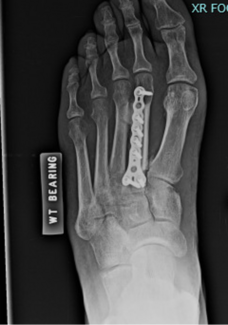

Jeffrey E. McAlister, DPM, FACFAS; Keegan A. Duelfer, DPM

Interest continues to grow in minimally invasive surgical (MIS) techniques throughout foot and ankle surgery in hopes of decreasing surgical trauma, mitigating certain risks, and perhaps allowing for earlier return to activity. Here the...